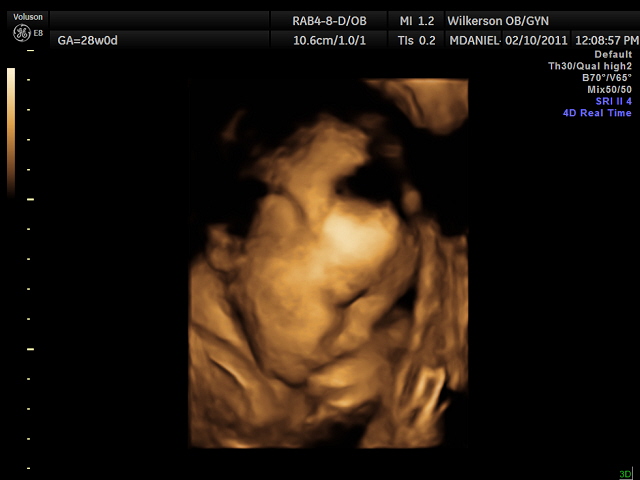

We had our 4-D ultrasound today. James would not cooperate at all but Jackson did. He was so precious he kept his hand over his face though. It was so neat. They are definitely cramped in there. We go back Monday and hopefully James will work with us. Here our a few pictures we have more but they are video rather than pictures.

Here is sweet Jackson: